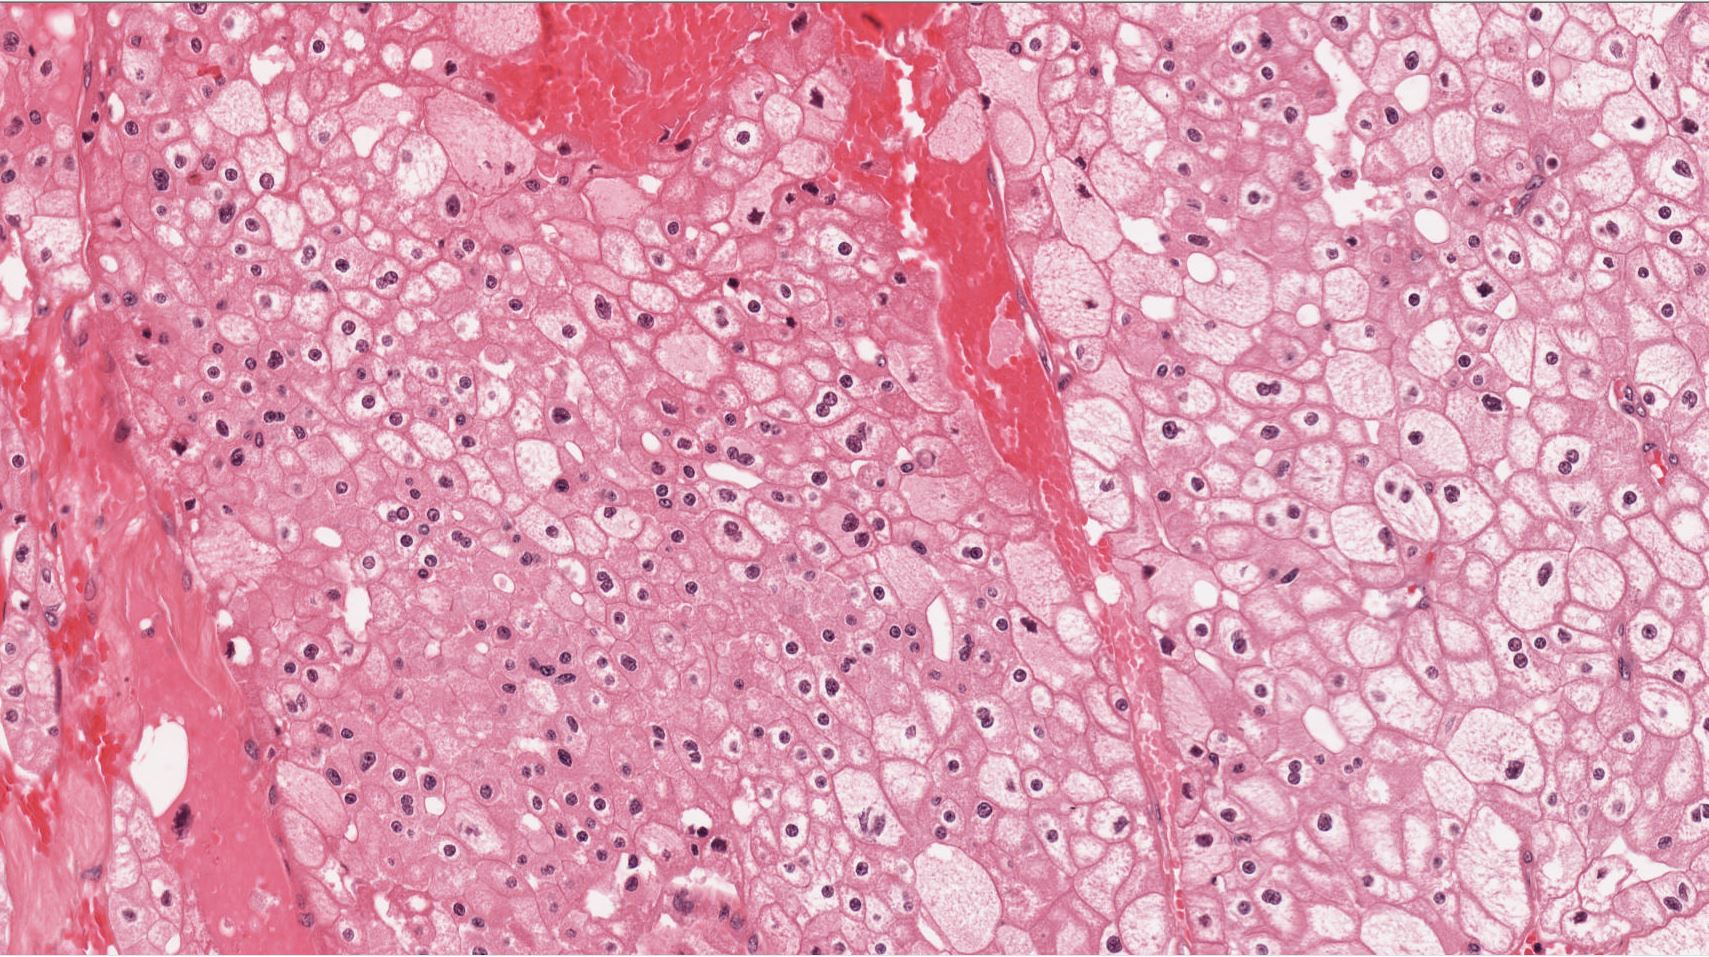

Renal tumor grading

Case ID: 544